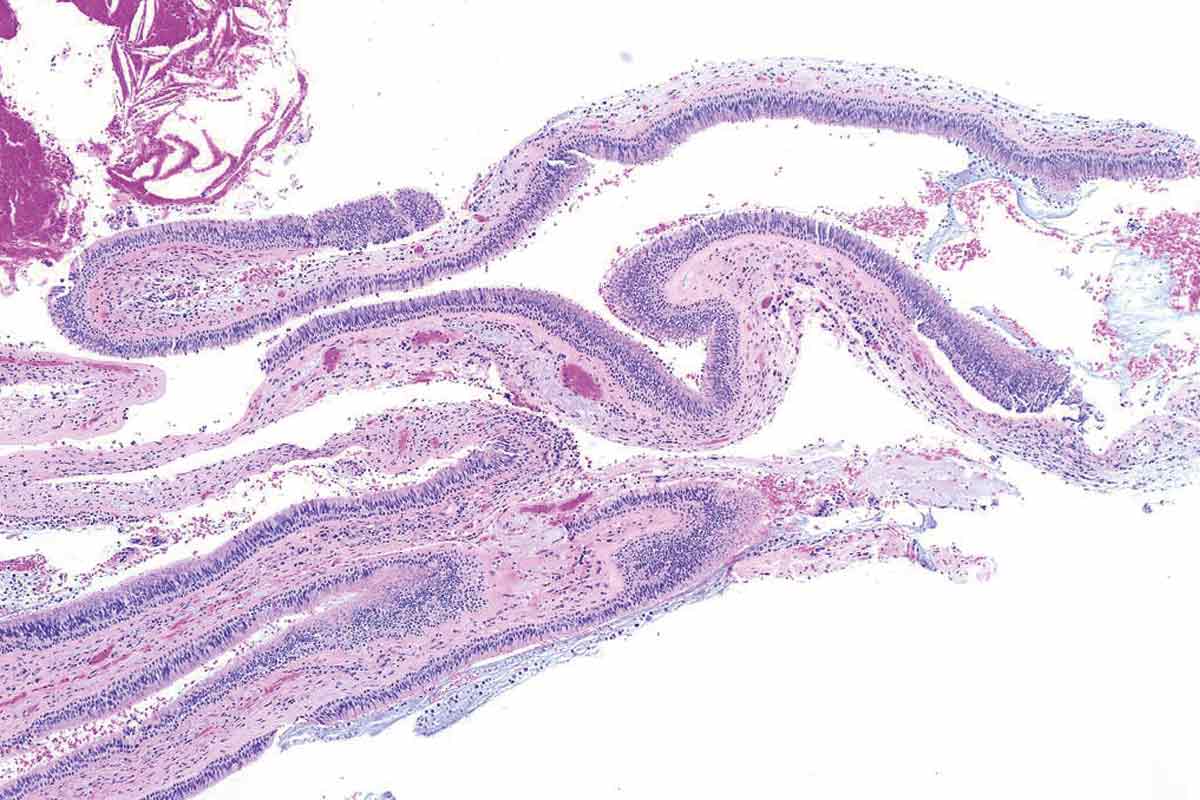

14/35 - Histological analysis shows a salivary retention cystMaxillary sinus cyst removal using the Crocodile Technique and subsequent lateral sinus lift - Dres. C. Scognamiglio and A. Perucchi